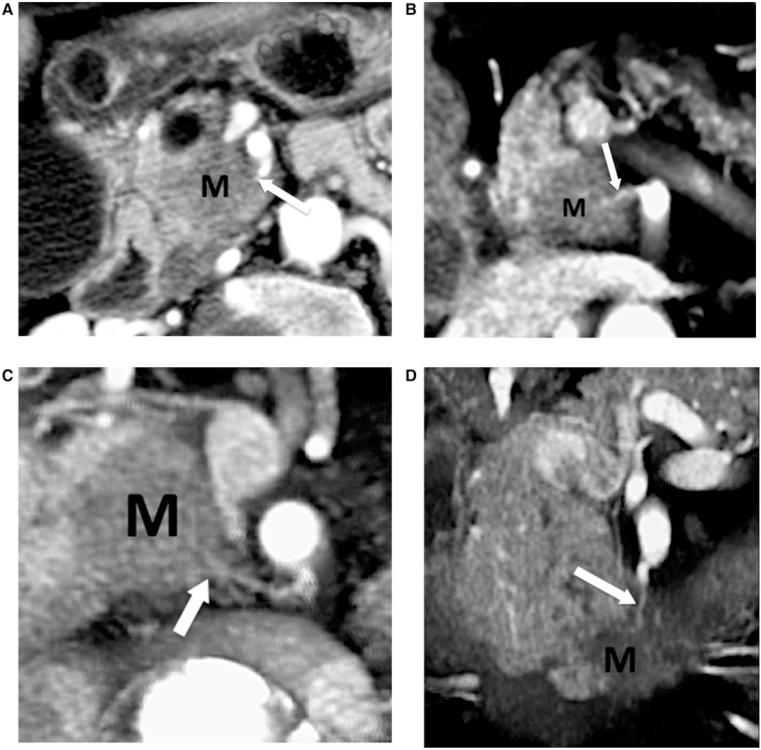

Extrapancreatic perineural spread in pancreatic adenocarcinoma contributes to poor outcomes, as it is known to be a major contributor to positive surgical margins and disease recurrence. However, current staging classifications have not yet taken extrapancreatic perineural spread into account. Four pathways of extrapancreatic perineural spread have been described that conveniently follow small defined arterial pathways. Small field of view three-dimensional (3D) volume-rendered multidetector computed tomography (MDCT) images allow visualization of small peripancreatic vessels and thus perineural invasion that may be associated with them. One such vessel, the posterior inferior pancreaticoduodenal artery (PIPDA), serves as a surrogate for extrapancreatic perineural spread by pancreatic adenocarcinoma arising in the uncinate process. This pictorial review presents the normal and variant anatomy of the PIPDA with 3D volume-rendered MDCT imaging, and emphasizes its role as a vascular landmark for the diagnosis of extrapancreatic perineural invasion from uncinate adenocarcinomas. Familiarity with the anatomy of PIPDA will allow accurate detection of extrapancreatic perineural spread by pancreatic adenocarcinoma involving the uncinate process, and may potentially have important staging implications as neoadjuvant therapy improves.

胰腺腺癌的胰外神经周围扩散会导致预后不良,因为它是手术切缘阳性和疾病复发的主要原因。然而,目前的分期分类尚未考虑胰外神经周围扩散。已经描述了胰外神经周围扩散的四条途径,这些途径方便地沿着明确的小动脉途径进行。小视野三维(3D)容积再现多排螺旋计算机断层扫描(MDCT)图像能够显示胰周小血管,从而显示可能与之相关的神经周围侵犯。其中一条血管,即胰十二指肠下后动脉(PIPDA),可作为钩突部胰腺腺癌胰外神经周围扩散的替代标志。本图像综述通过3D容积再现MDCT成像展示了PIPDA的正常和变异解剖结构,并强调了其作为诊断钩突腺癌胰外神经周围侵犯的血管标志的作用。熟悉PIPDA的解剖结构将有助于准确检测累及钩突部的胰腺腺癌的胰外神经周围扩散,并且随着新辅助治疗的改进,可能对分期有重要意义。